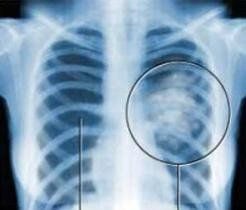

胸透胸透全稱螢光透視,為常用X線檢查方法。它是利用X線具有穿透性、螢光性和攝影效應的特性,使人體在螢屏上形成影像,由於人體組織有密度和厚度的差別,當X線穿透人體不同組織時,X線被吸收的程度不同,所以到達螢屏上的X線量就有差異,形成黑白對比不同的影像,為醫生的診斷提供依據。

主要看心,肝,肺有無異常,最主要是發現結核

胸透主要用於檢查診斷肺部疾病、心臟的大小、肋骨、胸膜、胸壁縱隔、支氣管。為減少X線的損害,患者做胸透檢查不宜過多,也不宜在短期內做多次重複檢查,特別是在胸透時不要一味地要求醫生看久一點、看仔細一些。